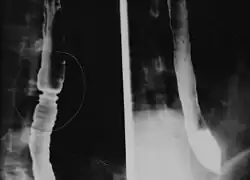

Eozynofilowe zapalenie przełyku (EE lub EoE, z ang. eosinophilic esophagitis) – przewlekła choroba zapalna przełyku, charakteryzująca się występowaniem izolowanych nacieków eozynofilowych w obrębie nabłonka przełyku oraz zmian makroskopowych (błon, pierścieni) wywołujących zwężenie światła przełyku i objawy kliniczne choroby[1]".

Zdrowy przełyk nie zawiera eozynofili, a ich obecność wskazuje na stan chorobowy. Początkowo EE uważano za jeden z objawów choroby refluksowej, obecnie jest uznawane za oddzielną jednostkę chorobową[2].